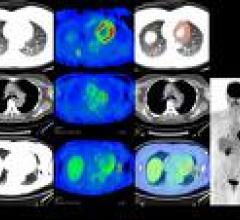

March 11, 2009 – When CT Laser Mammography (CTLM) is used as an adjunct to mammography in heterogeneously and…

A National Council on Radiation Protection and Measurement (NCRP) report stated that the U.S. population is now…

February 26, 2009 - In 2006, Americans were exposed to more than seven times as much ionizing radiation from medical…